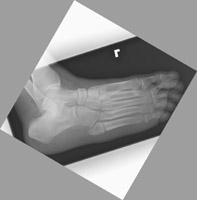

- Click on the image for a larger versionDAP and oblique radiographs of the foot. This patient demonstrates a fracture of the distal aspect of the fifth metatarsal.